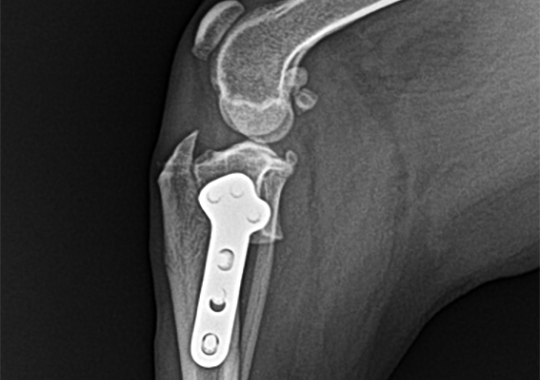

슬개골 탈구 수술법

본원에서는 같은 슬개골 탈구라고 해서 모든 환자들에게 획일적인 수술법을 시행하지 않습니다. 상담과 진단을 통해 파악한 탈구 및 변형 정도에 따라 환자들에게 가장 적합한 수술법으로 수술을 시행합니다.

양측 슬개골 탈구

양측 4등급 슬개골 탈구 교정 (DFO) 및 좌측 십자인대 교정

슬개골 활차구 치환술

BASIC 수술법

· 활차구성형술

· 경골결절변위술

· 지대중첩술

대퇴골절골술 (DFO)

대퇴골 변형이 심한 경우, 추가적으로 시행

활차구 치환술 (PGR)

슬개골 탈구 교정 시 필요한 활차구가 망가지거나

일반적인 수술이 불가능할 때 인공적으로 활차구를

만들어주는 수술법